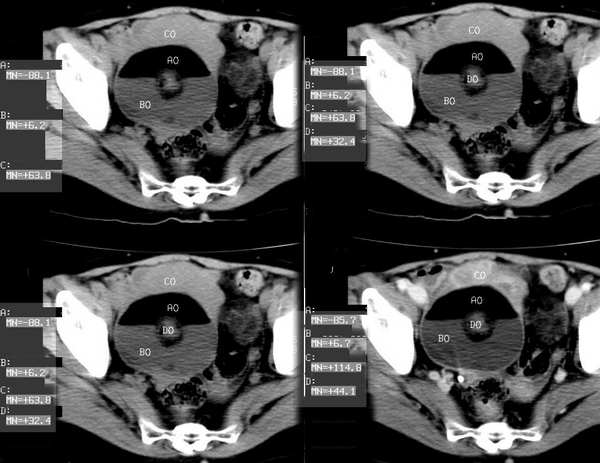

女,55岁,因下腹胀痛2月,b超发现盆腔包块7天,而入院,检查:右侧附件如女拳头大小包块,活动差,轻压痛,质中,子宫稍正常缩小,彩超示子宫4.9cmx2.6cmx2.3cm ,右侧附件包块示:8.7cmx9.1cmx6.3cm 的混合性回声,脂质分层征

囊性畸胎瘤的液-液征,增强瘤结节强化。

畸胎瘤,可见典型脂肪-液体征象。

右侧肿块前壁的带状软组织密度影我认为是肠管所致,该部位的小肠肠襻由于受到肿瘤的推移呈水平样排列,这样在ct扫描时相邻的肠壁在某些层面上可以呈现宽带状软组织密度影。

良性畸胎瘤伴出血。

畸胎瘤,脂-液分层